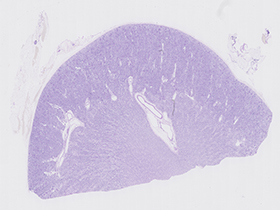

Riñón (tinción de PAS)